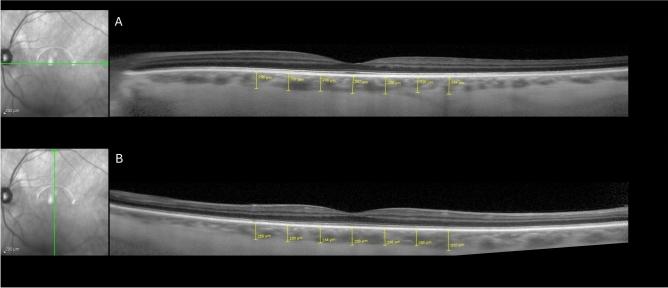

Frontotemporal lobar degeneration with tauopathy (FTLD-Tau) can present clinically similar to Alzheimer's disease but lacks a biomarker. Alzheimer's disease has been associated with choroidal thinning compared to controls. We compared the choroid of 25 probable FTLD-Tau (pFTLD-Tau) patients (42 eyes), 26 biomarker-determined probable Alzheimer's disease neuropathologic change (pADNC) patients (49 eyes), and 53 normal controls (80 eyes). Cerebrospinal fluid biomarkers determined presence of ADNC. All pFTLD-Tau patients had a syndrome highly associated with FTLD-Tau. Optical coherence tomography was performed with masked manual choroidal thickness (CT) measurements. With Image J, binarized images determined the choroidal vascularity index (CVI). Linear regression with generalized estimating equations to account for inter-eye correlation was performed. For pFTLD-Tau, pADNC, and controls, the subfoveal CT was 308.9, 286.0, and 301.5 μm, and CVI was 0.72, 0.72, and 0.73, respectively (all p > 0.05 for each group comparison). Adjusting for demographics, the CT and CVI were not significantly different between groups, including 13 CT measurement locations (all p > 0.05). Among pADNC patients, an exploratory analysis found a correlation between CVI and disease duration (Pearson r = 0.32, p = 0.04). We found no significant difference of CT or CVI between pFTLD-Tau, pADNC, and controls. Additional studies are warranted to evaluate how CVI relates to ADNC.

伴有tau蛋白病的额颞叶变性(FTLD-Tau)在临床上可能与阿尔茨海默病相似,但缺乏生物标志物。与对照组相比,阿尔茨海默病与脉络膜变薄有关。我们比较了25例可能的FTLD-Tau(pFTLD-Tau)患者(42只眼)、26例经生物标志物确定为可能的阿尔茨海默病神经病理改变(pADNC)患者(49只眼)和53名正常对照者(80只眼)的脉络膜情况。脑脊液生物标志物确定了ADNC的存在。所有pFTLD-Tau患者都有一种与FTLD-Tau高度相关的综合征。采用遮蔽式手动脉络膜厚度(CT)测量进行光学相干断层扫描。使用Image J软件,通过二值化图像确定脉络膜血管指数(CVI)。采用广义估计方程进行线性回归以考虑双眼间的相关性。对于pFTLD-Tau、pADNC和对照组,黄斑中心凹下CT分别为308.9、286.0和301.5μm,CVI分别为0.